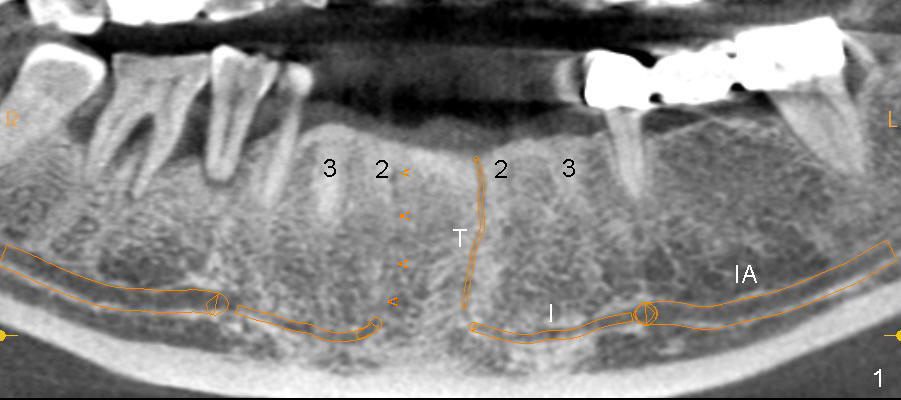

The incisive canal (Fig.1,2: I) is the anterior extension of the inferior alveolar canal (IA) after the latter gives rise to the mental nerve (circle). The terminal segment of the incisive canal (T or arrowheads in Fig.1) is located between the lower central (1) and lateral (2) incisors (3: lower canine).